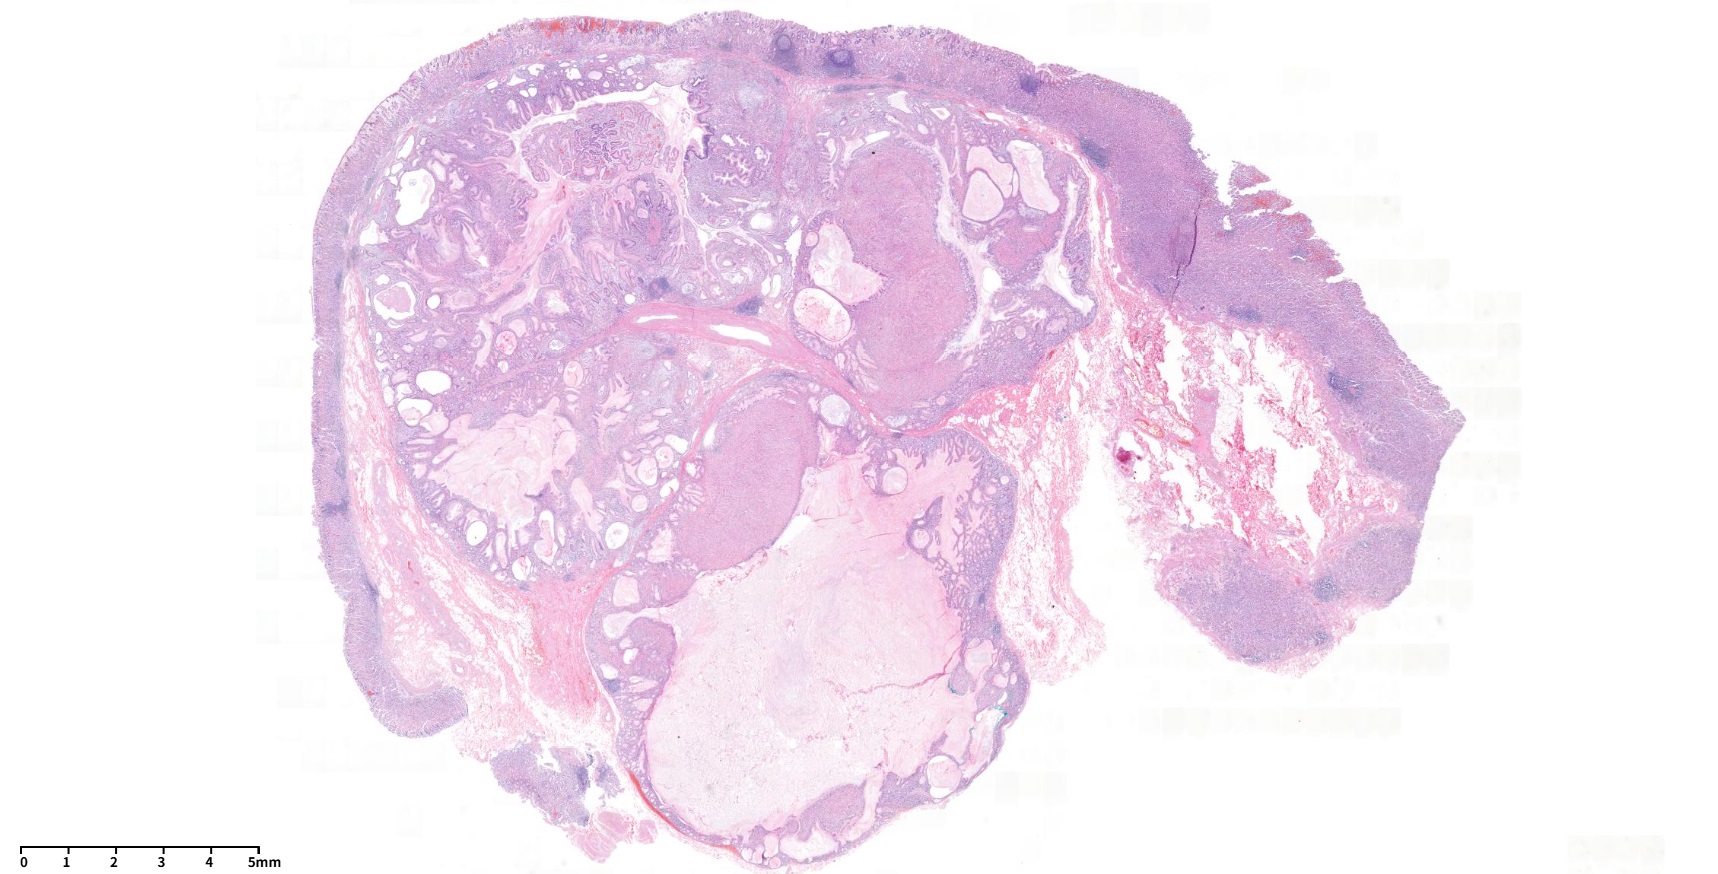

60¼¼ ³²¼ºÀÌ °Ç°­°ËÁø ³»½Ã°æ¿¡¼­ ¿ì¿¬È÷ ¹ß°ßµÈ À§ÀúºÎÀÇ 3cmÅ©±âÀÇ umbilicated ulcer¸¦ µ¿¹ÝÇÑ Á¡¸·ÇÏÁ¾¾ç ¼Ò°ßÀ¸·Î ÀǷڵǾú´Ù. ³»½Ã°æ °Ë»ç ´ç½Ã Á¶Á÷°Ë»ç ºÎÀ§ Áß ÇÑ °÷¿¡¼­ white thick mucinous materialÀÌ »ßÁ®³ª¿À´Â ¼Ò°ßÀÌ º¸¿´°í (»çÁø 1½Ã ¹æÇâ) ÂðµæÇÑ ´À³¦ÀÇ Á©¸®°°±âµµ ÇßÁö¸¸ Æ÷¼ÁÀ¸·Î ÀâÈ÷Áö´Â ¾Ê´Â´Ù´Â ¼Ò°ßÀÌ ±â¼úµÇ¾î ÀÖ¾ú´Ù. ¿ÜºÎ Á¶Á÷°Ë»ç °á°ú´Â stromal cell proliferation in lamina propria¿´°í ¾Ç¼º GIST (gastrointestinal stromal tumor) °¡´É¼ºÀÌ °í·ÁµÇ¾ú´Ù. ÀÇ·Ú ÈÄ ¿ÜºÎ ½½¶óÀ̵å ÀçÆÇµ¶ÇÑ ¼Ò°ßÀº Spindle cell tumor. differential diagnosis: GISTÀ̾ú´Ù. ³»½Ã°æ Àç°ËÀ» ÇÏ¿´°í À°¾È ¼Ò°ßÀº ºñ½ÁÇßÀ¸¸ç Á¶Á÷°Ë»ç Àç°ËÀº Chronic gastritis, active, with erosion, No definite submucosal tissue included·Î º¸°íµÇ¾úÀ¸¸ç DOG-1°ú C-KIT (CD 117)¿¡ ´ëÇÑ ¸é¿ªÇü±¤¿°»öÀº À½¼ºÀ̾ú´Ù. CT¸¦ ½ÃÇàÇÏ¿´À¸¸ç À§ÀúºÎ¿¡ ¾à 3 cmÀÇ endophytic mass°¡ ÀÖÀ¸¸ç central umbilicationÀÌ ÀÖ¾úÀ¸¸ç Á¤»ó mucosa·Î µ¤¿©ÀÖ¾î Á¡¸·ÇÏÁ¾¾çÀÇ °¡´É¼ºÀÌ ÀÖ´Â °ÍÀ¸·Î ÆÇµ¶µÇ¾ú´Ù. ºñ·Ï Á¶Á÷°Ë»ç¿¡¼­ È®ÀεÇÁö´Â ¾Ê¾ÒÀ¸³ª spindle cell proliferationÀÌ È®ÀÎµÈ ¹Ù ÀÖ°í ³»½Ã°æ À°¾È¼Ò°ß¿¡¼­ Áß¾ÓÀÇ Ç¥¸éÀÌ ºÒ±ÔÄ¢ÇÑ ÇÔ¸ôºÎ°¡ ÀÖ¾úÀ¸¹Ç·Î GISTÀÇ °¡´É¼ºÀ» °í·ÁÇÏ¿© ¿Ü°ú ÀÇ·ÚÇÏ¿© ½û±âÀýÁ¦¼úÀ» ÇÏ¿´´Ù. ÃÖÁ¾ º´¸® °á°ú´Â Herniated gastric mucosa with marked smooth muscle proliferation in submucosa, consistent with hamartomatous inverted polyp (1.7x1.6 cm)À̾úÀ¸¸ç desmin ¸é¿ªÇü±¤¿°»öÀº ¾ç¼ºÀ̾ú´Ù. À§ ¼Ó¸»¸² °ú¿ÀÁ¾¼º ¿ëÁ¾ (gastric inverted hamartomatous polyp, GIHP)Àº À§Á¡¸·ÇÏÃþ¿¡¼­ À§»ùÀÌ Áõ½ÄµÇ°í ³¶¼º È®ÀåÀ» º¸ÀÌ´Â °ÍÀ» Ư¡À¸·Î ÇÏ´Â ÁúȯÀÌ´Ù. º´¸®ÇÐÀûÀ¸·Î ÆòȰ±Ù Áõ½ÄÀ» º¸ÀÏ ¼ö ÀÖ´Ù. ÀϹÝÀûÀÎ °ú¿ÀÁ¾¼º ¿ëÁ¾ÀÌ ¿Ü¼ºÀå(exophytic growth)À» º¸ÀÌ´Â °Í¿¡ ºñÇÏ¿© GIHP´Â ³»¼ºÀå(endophytic growth)À» º¸ÀδÙ. ³»½Ã°æ ¼Ò°ß¿¡¼­ Ç¥¸éÀ¸·ÎºÎÅÍ ¿ìÀ¯°°Àº ¹Â½ÅÀÌ ¹èÃâµÉ ¼ö ÀÖ´Ù. ÃÊÀ½ÆÄ ³»½Ã°æ ¼Ò°ßÀº À̼Ҽº ÃéÀå Á¶Á÷°ú ±¸ºÐÀÌ ¾î·Æ´Ù. ¾à 20%ÀÇ ¾Ç¼ºÈ­ °¡´É¼ºÀÌ ÀÖÀ¸¹Ç·Î 2cm À̻󿡼­´Â ÀýÁ¦¼úÀ» ±ÇÇÑ´Ù.

Stomach, wedge resection: Herniated gastric mucosa with marked smooth muscle proliferation in submucosa, consistent with hamartomatous inverted polyp (1.7x1.6 cm)

GIHPs are a distinct entity characterized by submucosal growth of hypertrophic glands with cystic dilatation. They are distinct from the other types of hamartomatous polyps, which have an exophytic configuration contrary to the endophytic nature of these polyps. On endoscopic examination, these are reported as solitary submucosal masses. On endoscopy, extrusion of milky mucinous material from the surface of the lesion and calcifications from the biopsy site may provide a clue to diagnosis. On histology, there is cystic proliferation of glands, which may be accompanied by smooth muscle proliferation, and formation of ectopic duct-like structures has also been reported. In addition, fibroblastic and neural proliferation may also be seen with glandular elements. Diagnosis of GIHP is difficult without pathologic examination and may mimic ectopic pancreas on endoscopy and endosonography. Certain features have been suggested on endoscopic ultrasound imaging, such as hyperechoic lesions with hypoechoic spots, which might be suggestive of GIHPs. En bloc removal is recommended in lesions >2 cm due to the associated malignant risk (up to 20% risk of malignancy). Though it is rare, Hirasaki et al have reported a case of GHIP associated with signet ring cell carcinoma.

Wedge resection: herniated gastric mucosa in the submucosa with cystic dilatation

Herniated gastric mucosa in the submucosa

Wedge resection: Inverted hyperplastic polyp with focal inflammatory myofibroblastic tumor-like stroma (1.3x1cm)